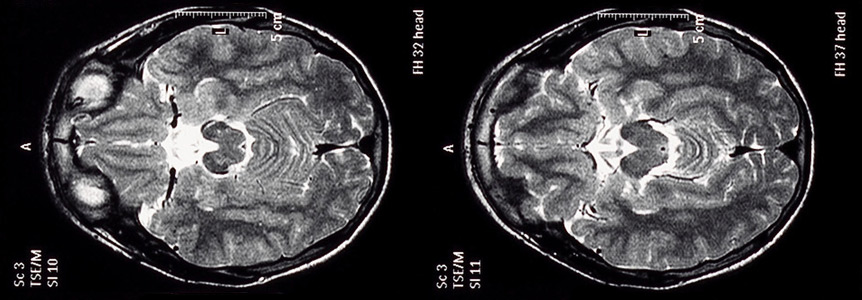

Manganese can have adverse health effects on the human brain.